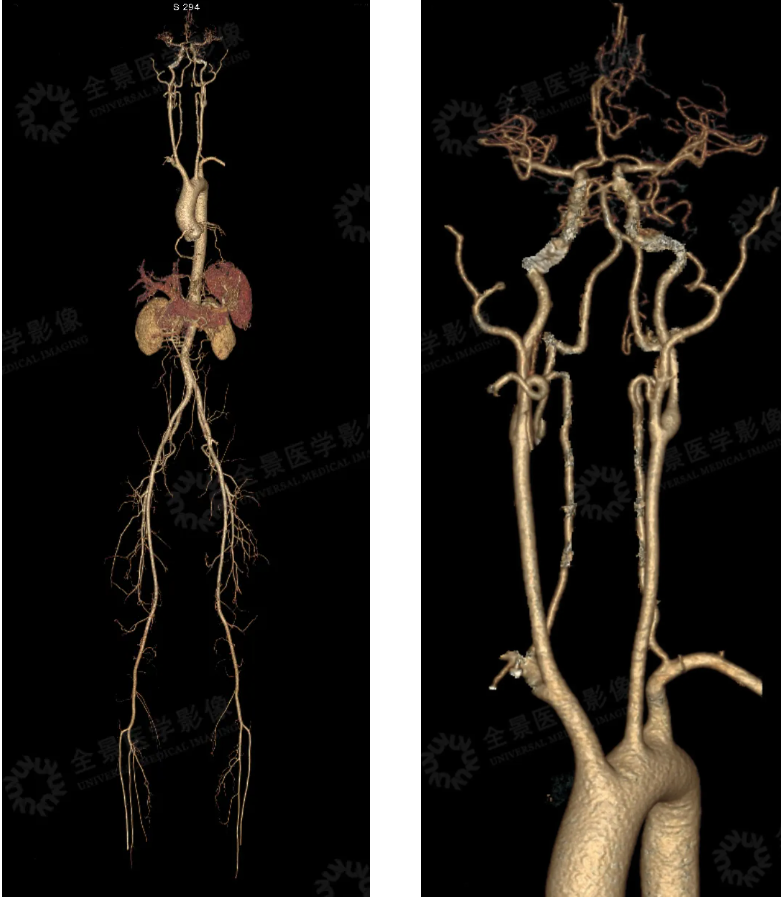

全身 CTA 示:

1. 双侧大脑后动脉 P3、P4 段纤细,周围多发细小血管。

2. 胸腹盆部 CTA 示:腹腔干夹层动脉瘤,远端管壁增厚并软斑形成,管腔重度狭窄,胰腺周围多发侧枝循环形成。(见下图)